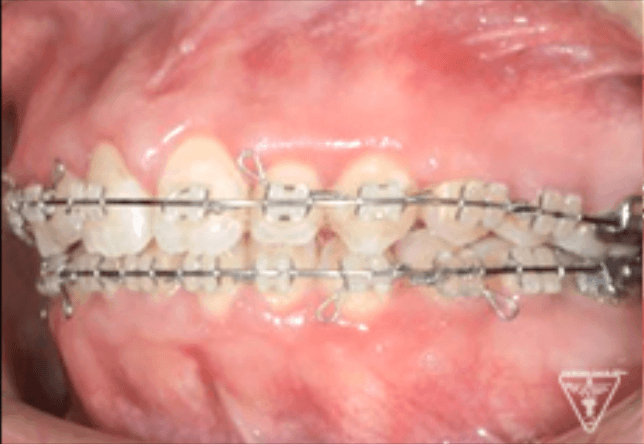

後期